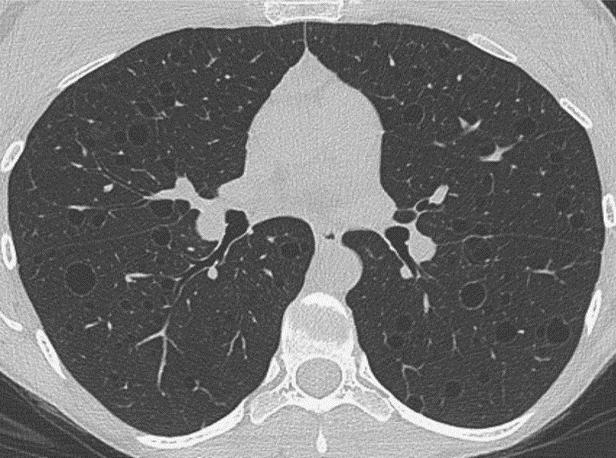

New Automated Method to Segment and Measure Lymphangioleiomyomatosis Lung Cysts in CT Images

This study addresses the cystic lung destruction in Lymphangioleiomyomatosis (LAM). Because LAM may progress over many years, doctors may use pulmonary function tests, exercise tests,